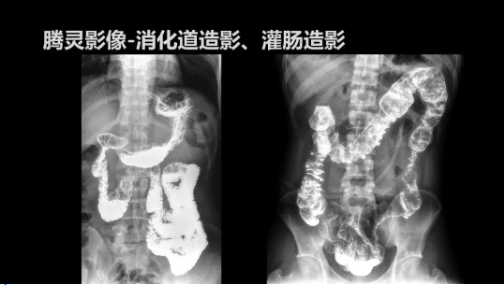

“騰靈”是安健科技的第四代動態(tài)DR產(chǎn)品,可實現(xiàn)全科室應用。如各類常規(guī)的X線檢查、消化道檢查、骨科檢查、婦科、兒科檢查等。此外,安健科技為“騰靈”在真正意義上實現(xiàn)多科室、多功能診斷進行了多項針對性設計。

此外,“騰靈”為了能夠幫助醫(yī)生更快速、有效的定位病灶,還增加了多項精準診斷保障功能,如支持動態(tài)觀察診斷,實時高清點片等?!膀v靈”透視切換高清點片曝光,捕捉關(guān)鍵病灶診斷僅需0.8s,同時還支持圖像局部放大,醫(yī)生可自由切換15’12’和9’三種放大模式,另外,“騰靈”還支持視頻保存、回放功能,幫助醫(yī)生在檢查結(jié)束后通過回放查看細節(jié),為醫(yī)生的診斷增加信心。